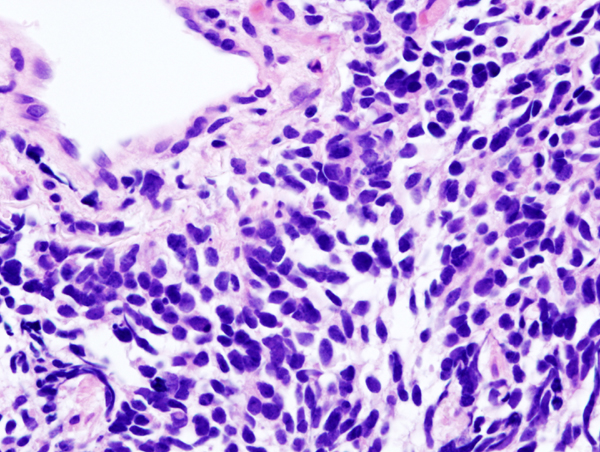

Histopathologic image of small cell carcinoma of the lung. CT-guided core needle biopsy. H & E stain.